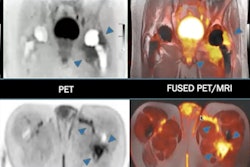

A large thrombus is seen in the left atrial appendage (LAA) behind the device on (A and B) the coronal PET and PET/cardiac MRI images as well as (C and D) the axial PET and PET/cardiac MRI images. (E and F) 2D balanced steady state free precession cines stacks in the coronal and axial planes have been combined into a single 3D dataset and fused with the 3D PET data. In these multimodality images, the PET and MR data are both displayed in 3D, creating a volumetric depiction of the heart and the thrombus/Cu-64 FBP8 containing LAA. Volume-rendered images in the oblique coronal and axial planes confirm the presence of thrombus in the LAA. (A to F) The thrombus produced by the closure device is contained within the LAA, and no evidence of thrombus is seen elsewhere in the heart or thorax. Image courtesy of JACC: Cardiovascular Imaging.SUVmax values in the LAA were significantly higher in patients with clots in the LAA than those without. An SUVmax threshold of 2.6 yielded a sensitivity of 100% and specificity of 84%, as evaluated by a radiologist with 15 years of experience, the researchers wrote.